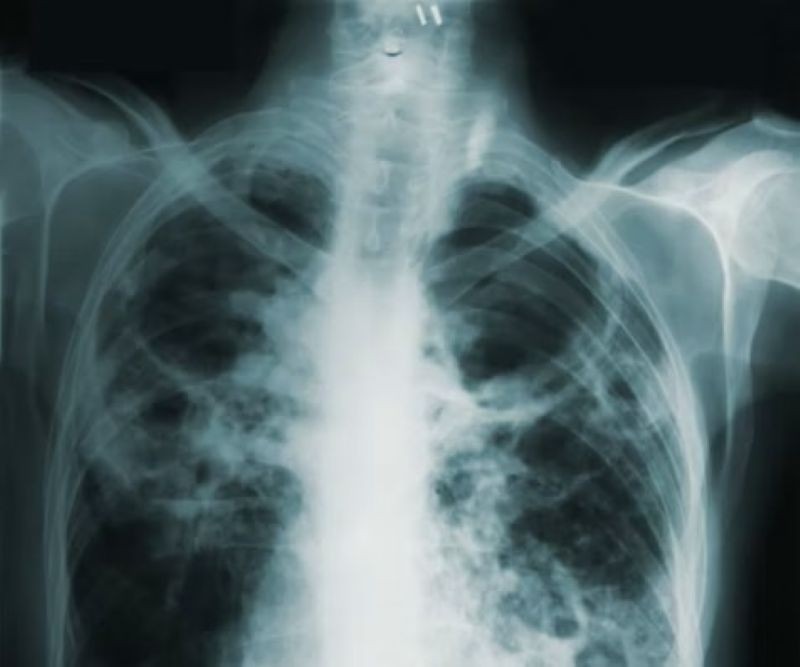

TB is caused by bacteria that most often affects the lungs. Every day, over 3,300 people die from the disease, with Southeast Asia accounting for nearly 40 per cent of deaths. Yet it is both preventable and treatable, including by using the antibiotic rifampicin.